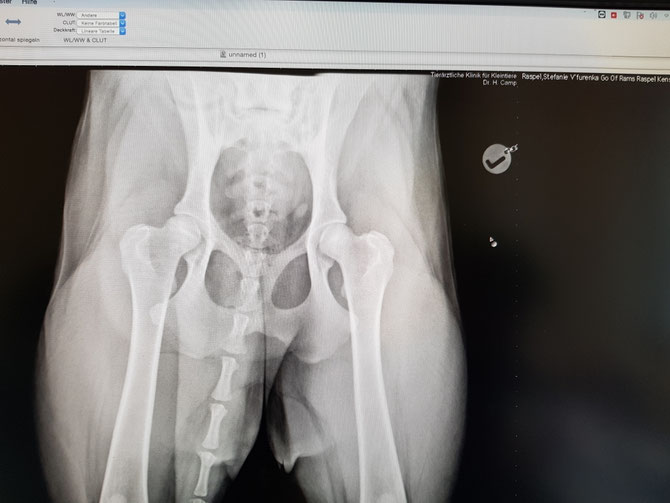

HD Auswertung

V'Furenka Go of RamsRaspel Kensha

HD A1